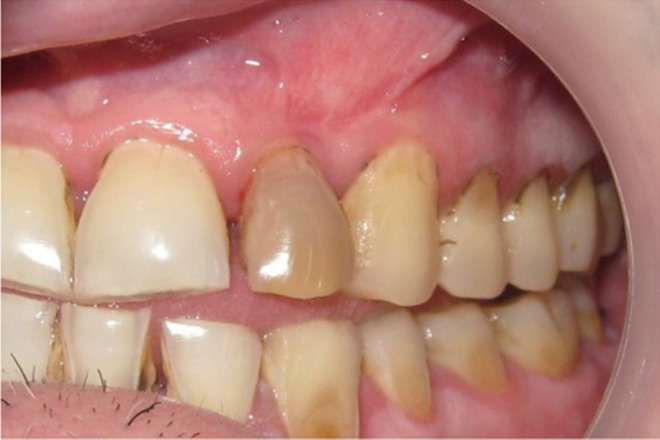

7). Closure of soft tissue flap was done with non resorbable black silk (3-0) suture using interrupted suturing technique. The sutures were removed 10 days after surgery. The patient was scheduled for regular recall intervals at 3, 6, 9 and 12 months. PRF and bone graft resulted in substantial amount of bone fill (

Figures 8a and 8b), and probing depth was reduced to 2 mm.